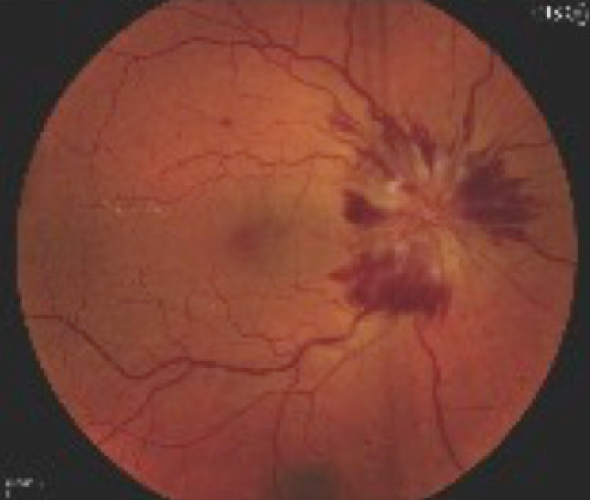

Figure 5. Severe right optic disc edema is seen only in advanced cases of thyroid-related compressive optic neuropathy.

Many times, medical therapy may reduce the disease burden in TED but not restore orbital and ocular function to the predisease state (Figures 5 and 6). As a result, rehabilitative surgery may be required. Unless the risk of permanent eye damage is suspected, orbital and periocular surgery should be avoided during the active phase to ensure the stability of surgical results. Surgical techniques and instrumentation have been greatly improved, now allowing surgery to be tailored for each patient. Preoperative orbital volumetric and orbital physiologic analysis may provide the adaptive surgeon the ability to better predict surgical outcomes. The introduction of intraoperative surgical navigation and instrumentation, such as piezoelectric bone removal systems, may afford safer, more strategic outcomes with orbital decompression (Figure 7). Algorithms developed for strabismus and eyelid surgery may improve ocular function and appearance.